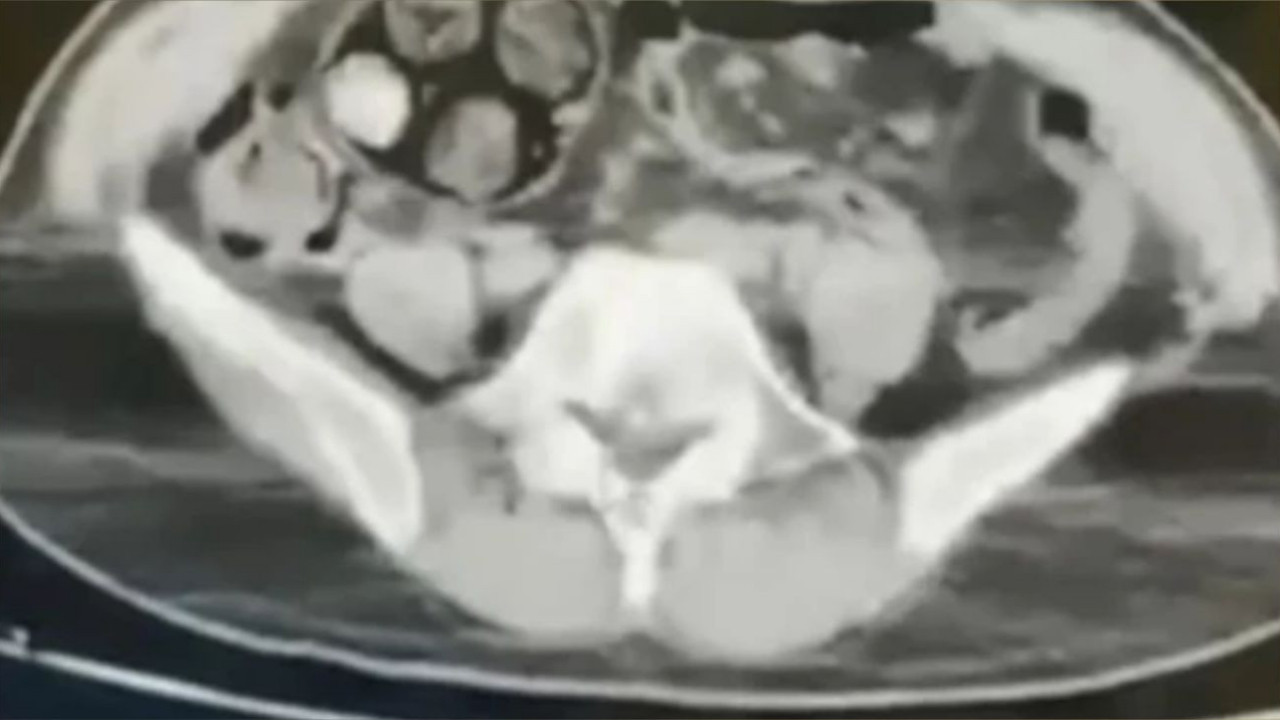

Bayburt Cumhuriyet Başsavcılığı koordinesinde Narkotik Suçlarla Mücadele Şube Müdürlüğü görevlilerince Narkotik Madde Kullanımı İmal ve Ticaretinin önlenmesi amacıyla yapılan analiz çalışmaları sonucunda durumundan şüphelenilen D.A. isimli İran uyruklu şahsın Bayburt Devlet Hastanesinde yapılan iç beden muayenesinde mide ve bağırsaklarında çok sayıda yabancı madde olduğu görüldü.

Şüpheli şahsın içinden 588,55 gram metamfetamin maddesi çıkarıldı. T.C.K madde 188 Uyuşturucu veya Uyarıcı Madde İmal ve Ticareti suçundan adli işlem yapılan şahıs çıkarıldığı mahkemece tutuklanarak cezaevine gönderildi.